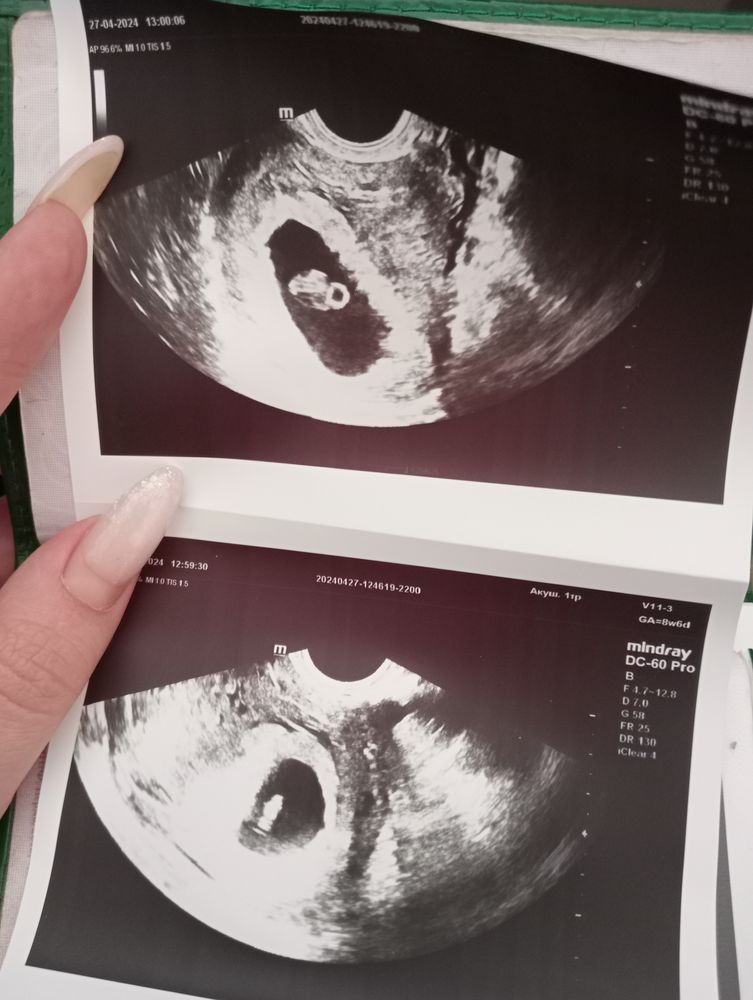

27.04 была на УЗИ, врач сказала никого не слушать, все хорошо, патологий не выявлено, ПЯ немного большевато, но сказали, что ничего страшного в этом нет, первый раз послушала сердечко малыша ❤

ПЯ: 26,6 мм

ЖМ: 4,5 мм

Эмбрион: 10мм, что соответствует 7 неделям

ЧСС: 126 уд./мин.